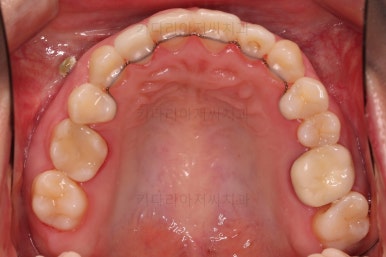

적절하게 디테일을 손보고 마무리를 합니다.

중간중간 보철된 치아도 있고, 위아래의 중앙선까지 100% 맞기는 힘든 상황이었지만 가급적이면 매우 잘 맞춰 드렸고요.

교합이라던지 가지런한 느낌도 좋네요.

우측만 위아래 뽑았지만 기능에는 문제 없이 교합을 마무리 했습니다.

부산치과교정 전후사진을 비교해 볼게요.

중심선도 원하시는만큼 갖추었고, 가지런한 느낌도 좋고요.

21개월만에 전반적으로 매우 만족할만한 치료 결과를 얻었습니다.